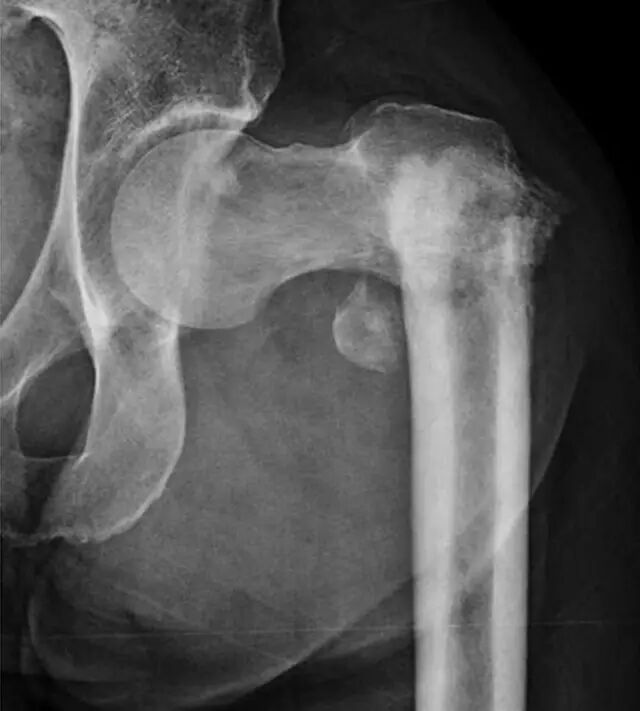

即使正确定位和技术上优秀的射线照片,一些骨折在X线片上是不可检测的,因为它们是无位移的。这些骨折有症状,并有相应的临床表现和受伤的机制,但他们没有明显的X光片。在本质上,X射线照片结果是假阴性的,因为该方法本身局限性不足以显示断裂。 射线照片上的急性骨折的检测通常需要它们在一定程度上移位。由于临床体征高度怀疑,通常需要进一步评估额外的成像,特别是如果这种成像的结果将影响临床管理。这样的例子有上了年纪的人或老年人在地面踉跄之后加上不能承受体重,髋部疼痛, 骨质疏松通常进一步增加了检测不位移性骨折的难度。放射线检查结果可能是阴性或模棱两可的,因为骨矿物的弥漫性损失使不位移性骨折线不太明显。因为近端股骨骨折的管理通常是手术,当根据临床表现的骨折的预测概率高时,通常进行进一步的CT或MRI评估。美国放射学会[12]建议对中年或老年患者进行MRI(等级9)CT(等级6)或放射性核素骨扫描(等级4),这些患者在放射照片显示阴性或不确定性,用CT与MRI的诊断优势以排除存在放射学上隐匿性髋骨骨折[13]。如果MRI不可用或者患者对MRI具有禁忌症,CT可以提供最佳选择。然而,MRI在检测骨髓水肿方面优越(图3)。骨扫描已应用于放射摄影术的初步诊断[14],但在我们的实践中最少使用,因为CT更为普遍。床旁超声检查最近被研究作为一种检测第五跖骨骨折的方法,基本上作为身体检查的延伸,并且与放射线照片相比显示出一些前景[15]。然而,在多发伤筛查情况下,超声检查的成像效果不如放射照相[16]。

图3A-65岁的男子在地面摔倒后,在射线照片上没有看到移位性骨折。

A,前后放射照片显示正常。侧视图也是正常的。患者抱怨右髋疼痛,无法承受体重或步行。

图3B-65岁的男子在地面摔倒后,在射线照片上没有看到移位性骨折。冠状T1加权MRI显示无错位股骨颈骨折。